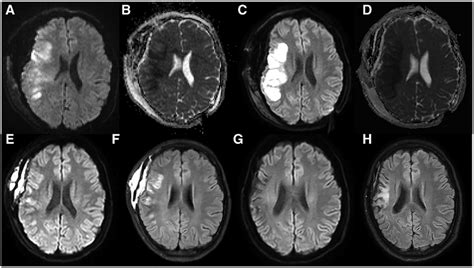

Let’s really zoom in on Brownian motion and diffusion because they’re the absolute superstars behind Diffusion-Weighted Imaging (DWI) . Imagine, if you will, a microscopic mosh pit of water molecules inside your body. They’re not just sitting still; they’re constantly vibrating, rotating, and translating, bumping into everything around them. This seemingly chaotic, random movement is what we call Brownian motion , a phenomenon first observed by botanist Robert Brown when he saw pollen grains jiggling in water. In our biological tissues, water molecules are diffusing through a complex maze of cells, fibers, and membranes. The rate and direction of this diffusion are incredibly sensitive to the tissue’s microstructure. If the water molecules are in a wide-open space, like cerebrospinal fluid (CSF) in the brain’s ventricles, they can move freely in all directions; this is called free diffusion . However, when these molecules encounter obstacles, like tightly packed cells in a tumor or the swollen cells in an ischemic stroke, their movement becomes restricted or hindered . It’s like trying to run through a dense forest versus an open field – your path is much more constrained in the forest. Diffusion-Weighted Imaging (DWI) is specifically designed to detect these changes in diffusion . It applies strong, rapidly switched magnetic field gradients during the MRI scan. These gradients act like a temporary ‘tag’ for the water molecules. A initial gradient pulse ‘tags’ the protons of water molecules. If a water molecule moves before a second, identical gradient pulse is applied, it will experience a different magnetic field strength, causing its signal to be out of phase and thus attenuated or lost. The more the water molecules move (i.e., the greater the diffusion), the more signal is lost. Conversely, if the molecules are restricted and haven’t moved much, they will maintain their phase coherence, and their signal will be preserved, appearing brighter on the DWI image. This mechanism is profoundly powerful because it allows us to visualize conditions that restrict water movement, often before any anatomical changes are apparent on conventional MRI. For example, in acute ischemic stroke, cellular energy failure leads to cytotoxic edema, causing cells to swell and restrict the extracellular space. This restricted movement of water is picked up almost immediately by DWI , showing up as bright lesions. This makes DWI an indispensable tool for early diagnosis, enabling rapid intervention that can significantly alter patient outcomes. So, guys, when you see a bright spot on a DWI scan, it’s not just random brightness; it’s a visual representation of water molecules struggling to move, giving us a crucial clue about the underlying tissue pathology. It’s all about that Brownian motion and how the environment affects its diffusion , beautifully captured by this advanced imaging technique. This detailed understanding of the microscopic world of water movement within biological tissues is what truly sets Diffusion-Weighted Imaging (DWI) apart as a diagnostic powerhouse, offering unparalleled insights into cellular health and disease processes.

Alright, let’s talk about something incredibly useful and quantitative in Diffusion-Weighted Imaging (DWI) : the Apparent Diffusion Coefficient (ADC) map . While raw DWI images, especially those with high b-values , show areas of restricted diffusion as bright, this brightness can sometimes be influenced by other factors, like T2 shine-through (where lesions that are simply very bright on T2-weighted images also appear bright on DWI, even if diffusion isn’t truly restricted). This can be confusing, right? That’s where the ADC map comes to the rescue! The ADC map is a quantitative image that’s derived from at least two DWI images acquired with different b-values (usually b =0 and a higher b -value, like 1000 s/mm²). Essentially, it’s a calculated image where the signal intensity in each pixel is directly proportional to the actual diffusion coefficient of water molecules in that specific tissue. This means the ADC map gives us a direct numerical value, often expressed in mm²/s, for how freely water molecules are diffusing. What’s super cool about the ADC map is that it’s largely independent of T2 effects. This means it provides a pure measure of diffusion . On an ADC map , areas with truly restricted diffusion (like acute stroke, highly cellular tumors, or pus in an abscess) will appear dark because their ADC values are low. Conversely, areas with facilitated diffusion (like cerebrospinal fluid, necrotic tissue, or vasogenic edema) will appear bright because their ADC values are high. This inversion of signal intensity compared to high b-value DWI images is key to its interpretation. So, guys, when a radiologist sees a bright lesion on a high b -value DWI image, they always cross-reference it with the corresponding ADC map . If the lesion is bright on DWI and dark on the ADC map , then you’ve got true restricted diffusion, which is highly indicative of acute pathology like ischemic stroke, where ADC values drop significantly within minutes to hours of onset. This combination – bright DWI and dark ADC – is often referred to as a “DWI-ADC mismatch” and is a hallmark for diagnosing acute ischemic stroke. In tumor characterization, ADC values can help distinguish between different types of tumors or even assess tumor cellularity. Highly cellular tumors tend to have lower ADC values because the dense packing of cells restricts water movement, while less cellular tumors or those with necrosis might have higher ADC values. The interpretation of ADC maps in various clinical scenarios is incredibly valuable. It helps in differentiating acute from chronic stroke, identifying abscesses (low ADC due to viscous pus and cellular debris), distinguishing epidermoid cysts from arachnoid cysts (epidermoids have very low ADC), and even assessing treatment response in oncology. A decrease in tumor cellularity after chemotherapy, for example, might be reflected as an increase in ADC values. So, the Apparent Diffusion Coefficient (ADC) map isn’t just another image; it’s a quantitative biomarker that provides indispensable diagnostic and prognostic information, making Diffusion-Weighted Imaging (DWI) an even more powerful tool in clinical practice.

Alright, guys, let’s get into the really impactful stuff: the clinical applications of Diffusion-Weighted Imaging (DWI) . This is where all that cool science we just talked about translates directly into saving lives and improving patient outcomes. DWI isn’t just a research tool; it’s a cornerstone of modern diagnostic radiology, providing critical information across a wide spectrum of medical conditions. Its unique sensitivity to microscopic water movement makes it invaluable in situations where early detection and precise characterization are paramount. Trust me, its utility in daily clinical practice is immense. One of the most famous and perhaps most critical applications of Diffusion-Weighted Imaging (DWI) is in the detection of acute ischemic stroke . As we briefly touched upon, DWI can detect areas of restricted diffusion within minutes to hours of stroke onset, long before conventional MRI or CT scans show any changes. This early detection is a game-changer because time is brain in stroke; rapid diagnosis allows for immediate intervention, such as thrombolytic therapy or mechanical thrombectomy, which can significantly reduce permanent brain damage and improve recovery. The classic finding of bright signal on high b -value DWI images coupled with low signal on ADC maps is virtually diagnostic for acute stroke. Without DWI , doctors would be flying blind for crucial hours, potentially missing the window for effective treatment. Beyond stroke, Diffusion-Weighted Imaging (DWI) plays a crucial role in tumor characterization . It helps differentiate between benign and malignant lesions, assess tumor cellularity, and even predict tumor aggressiveness. Highly cellular tumors, like lymphomas or glioblastomas, often show restricted diffusion (low ADC values) due to the dense packing of cells and limited extracellular space. This contrasts with cysts or necrotic areas within tumors, which typically have higher ADC values. DWI can also be used to monitor treatment response in oncology; a rise in ADC values after chemotherapy or radiation therapy can indicate a reduction in tumor cellularity and effective treatment. This makes it an invaluable tool for guiding cancer therapy. Another significant application is in the detection and characterization of infections and inflammation , particularly abscesses in the brain or spinal cord. Pus, being a viscous fluid filled with cellular debris, often exhibits restricted diffusion on DWI (low ADC), helping to differentiate an abscess from a necrotic tumor or other cystic lesions. This distinction is vital for guiding appropriate treatment – surgery and antibiotics for an abscess versus different protocols for a tumor. DWI is also increasingly used in neurodegenerative diseases like Alzheimer’s disease and Parkinson’s disease, where it can provide insights into white matter integrity and track disease progression, often using advanced techniques like DTI. Furthermore, it has applications in epilepsy for identifying epileptogenic foci, in multiple sclerosis for detecting subtle demyelinating lesions, and even in abdominal and pelvic imaging for detecting and characterizing various lesions, including liver metastases and prostate cancer. The versatility of Diffusion-Weighted Imaging (DWI) truly underscores its importance. From acute emergencies to chronic disease management and cancer care, DWI provides unique, non-invasive insights into tissue microstructure and pathology, helping clinicians make more informed decisions and ultimately improving patient care across a vast array of medical specialties. It’s a remarkable testament to how understanding fundamental physics can lead to such profound practical benefits in medicine, offering a window into the body’s cellular secrets that was once unimaginable.